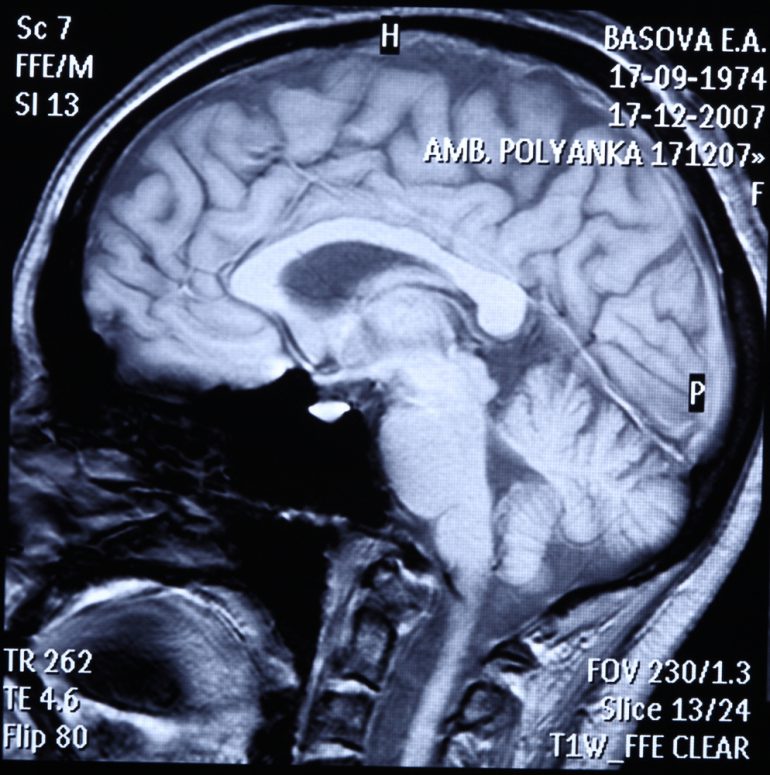

Pour ce faire, un test de 360 essais, conjuguant effort mental et physique, a été réalisé sous l’œil d’un scanner. Les 20 participants, la tête dans un appareil d’IRM fonctionnelle, devaient exécuter plusieurs séries de tâches leur permettant d’accumuler des gains.

Grâce aux images obtenues, l’équipe a identifié dans la profondeur du cerveau un système motivationnel général, c’est-à-dire une structure capable d’activer n’importe quel type d’effort, qu’il soit mental (comme se concentrer sur ce qu’on fait) ou physique (comme soulever une charge): le striatum ventral. Celui-ci s’activerait ainsi en proportion de la somme en jeu et il semble que plus le degré de motivation est fort, plus l’activation est importante.